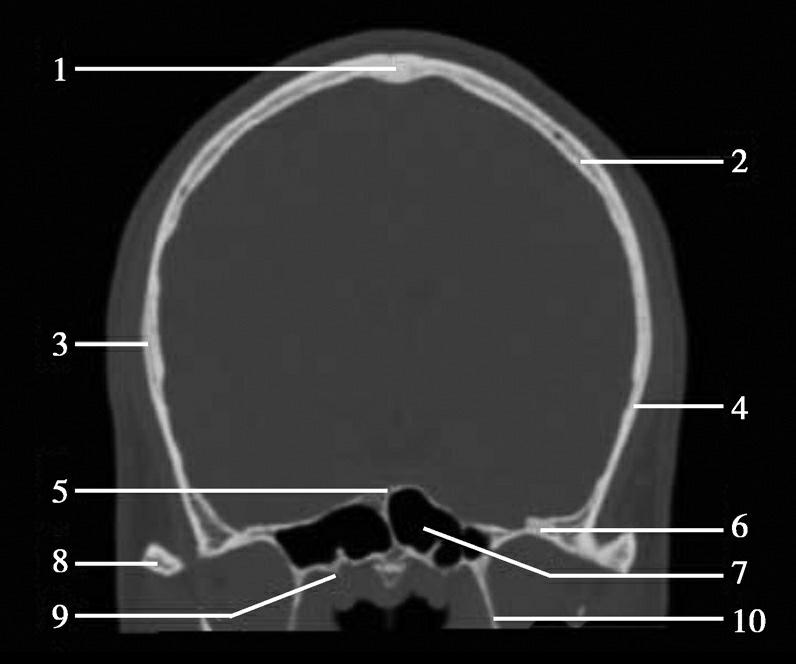

重要结构:胼胝体、垂体、中脑导水管、扣带回、中央沟、第三脑室、斜坡(图1-2-59、图1-2-60)。

图1-2-59 正中矢状面CT

A.矢状面;B.矢状面标注

1.中央沟;2.扣带回;3.胼胝体体部;4.侧脑室;5.中脑;6.胼胝体膝部;7.穹隆;8.第三脑室;9.胼胝体压部;10.垂体;11.中脑导水管;12.第四脑室;13.脑桥;14.蝶窦;15.斜坡;16.小脑扁桃体;17.延髓

图1-2-60 正中矢状面骨窗CT

1.顶骨;2.枕骨;3.斜坡;4.额骨;5.蝶鞍

此层面可显示胼胝体全貌,它位于层面中央区域,是呈上凸下凹的弧形结构,由前向后分为嘴、膝、体和压四部分。扣带回环绕胼胝体上方,扣带沟位于扣带回的上方。大脑半球中部和后部分别可见较深且恒定的中央沟和顶枕沟。中央沟为是额叶顶叶分界标志。

胼胝体下方为侧脑室及穹窿,第三脑室借穹窿与前上方的侧脑室体部分开,背侧丘脑的内侧面以及中脑顶盖分别为第三脑室的外侧壁和底。第三脑室向前籍室间孔与侧脑室相通,向下经中脑导水管通第四脑室。中脑腔狭窄呈管状,即称为中脑导水管,中脑导水管畸形,常见者为导水管的分叉畸形和狭窄,其次可见中脑导水管膈膜,造成先天性脑积水。

脑干由中脑、脑桥和延髓组成,自第三脑室底向下后稍斜行,移行于颈髓。由上至下,脑干腹侧可见脚间池、桥前池和延髓池,脑干背侧可见大脑大静脉池、四叠体池和小脑延髓池。

垂体位于蝶鞍内,其前部为腺垂体,后上部分为神经垂体。垂体下方为鞍底及蝶窦,上缘因鞍膈存在而平直,垂体借垂体柄向上连于丘脑下部。垂体的前上方见视交叉和视束。斜坡作为前颅窝底的重要组成部分与多个重要结构相比邻,矢状位呈三角形,颅内肿瘤或颅外鼻咽部恶性肿瘤均可侵犯至此,原发肿瘤常见为脊索瘤。小脑幕居枕叶和小脑之间,向后下连接窦汇,向前至中脑后方游离,称小脑幕切迹。小脑幕下方为小脑扁桃体。成年人小脑扁桃体下缘由枕骨大孔向下疝入椎管超过5mm称为Chiari畸形,以矢状位显示最佳。